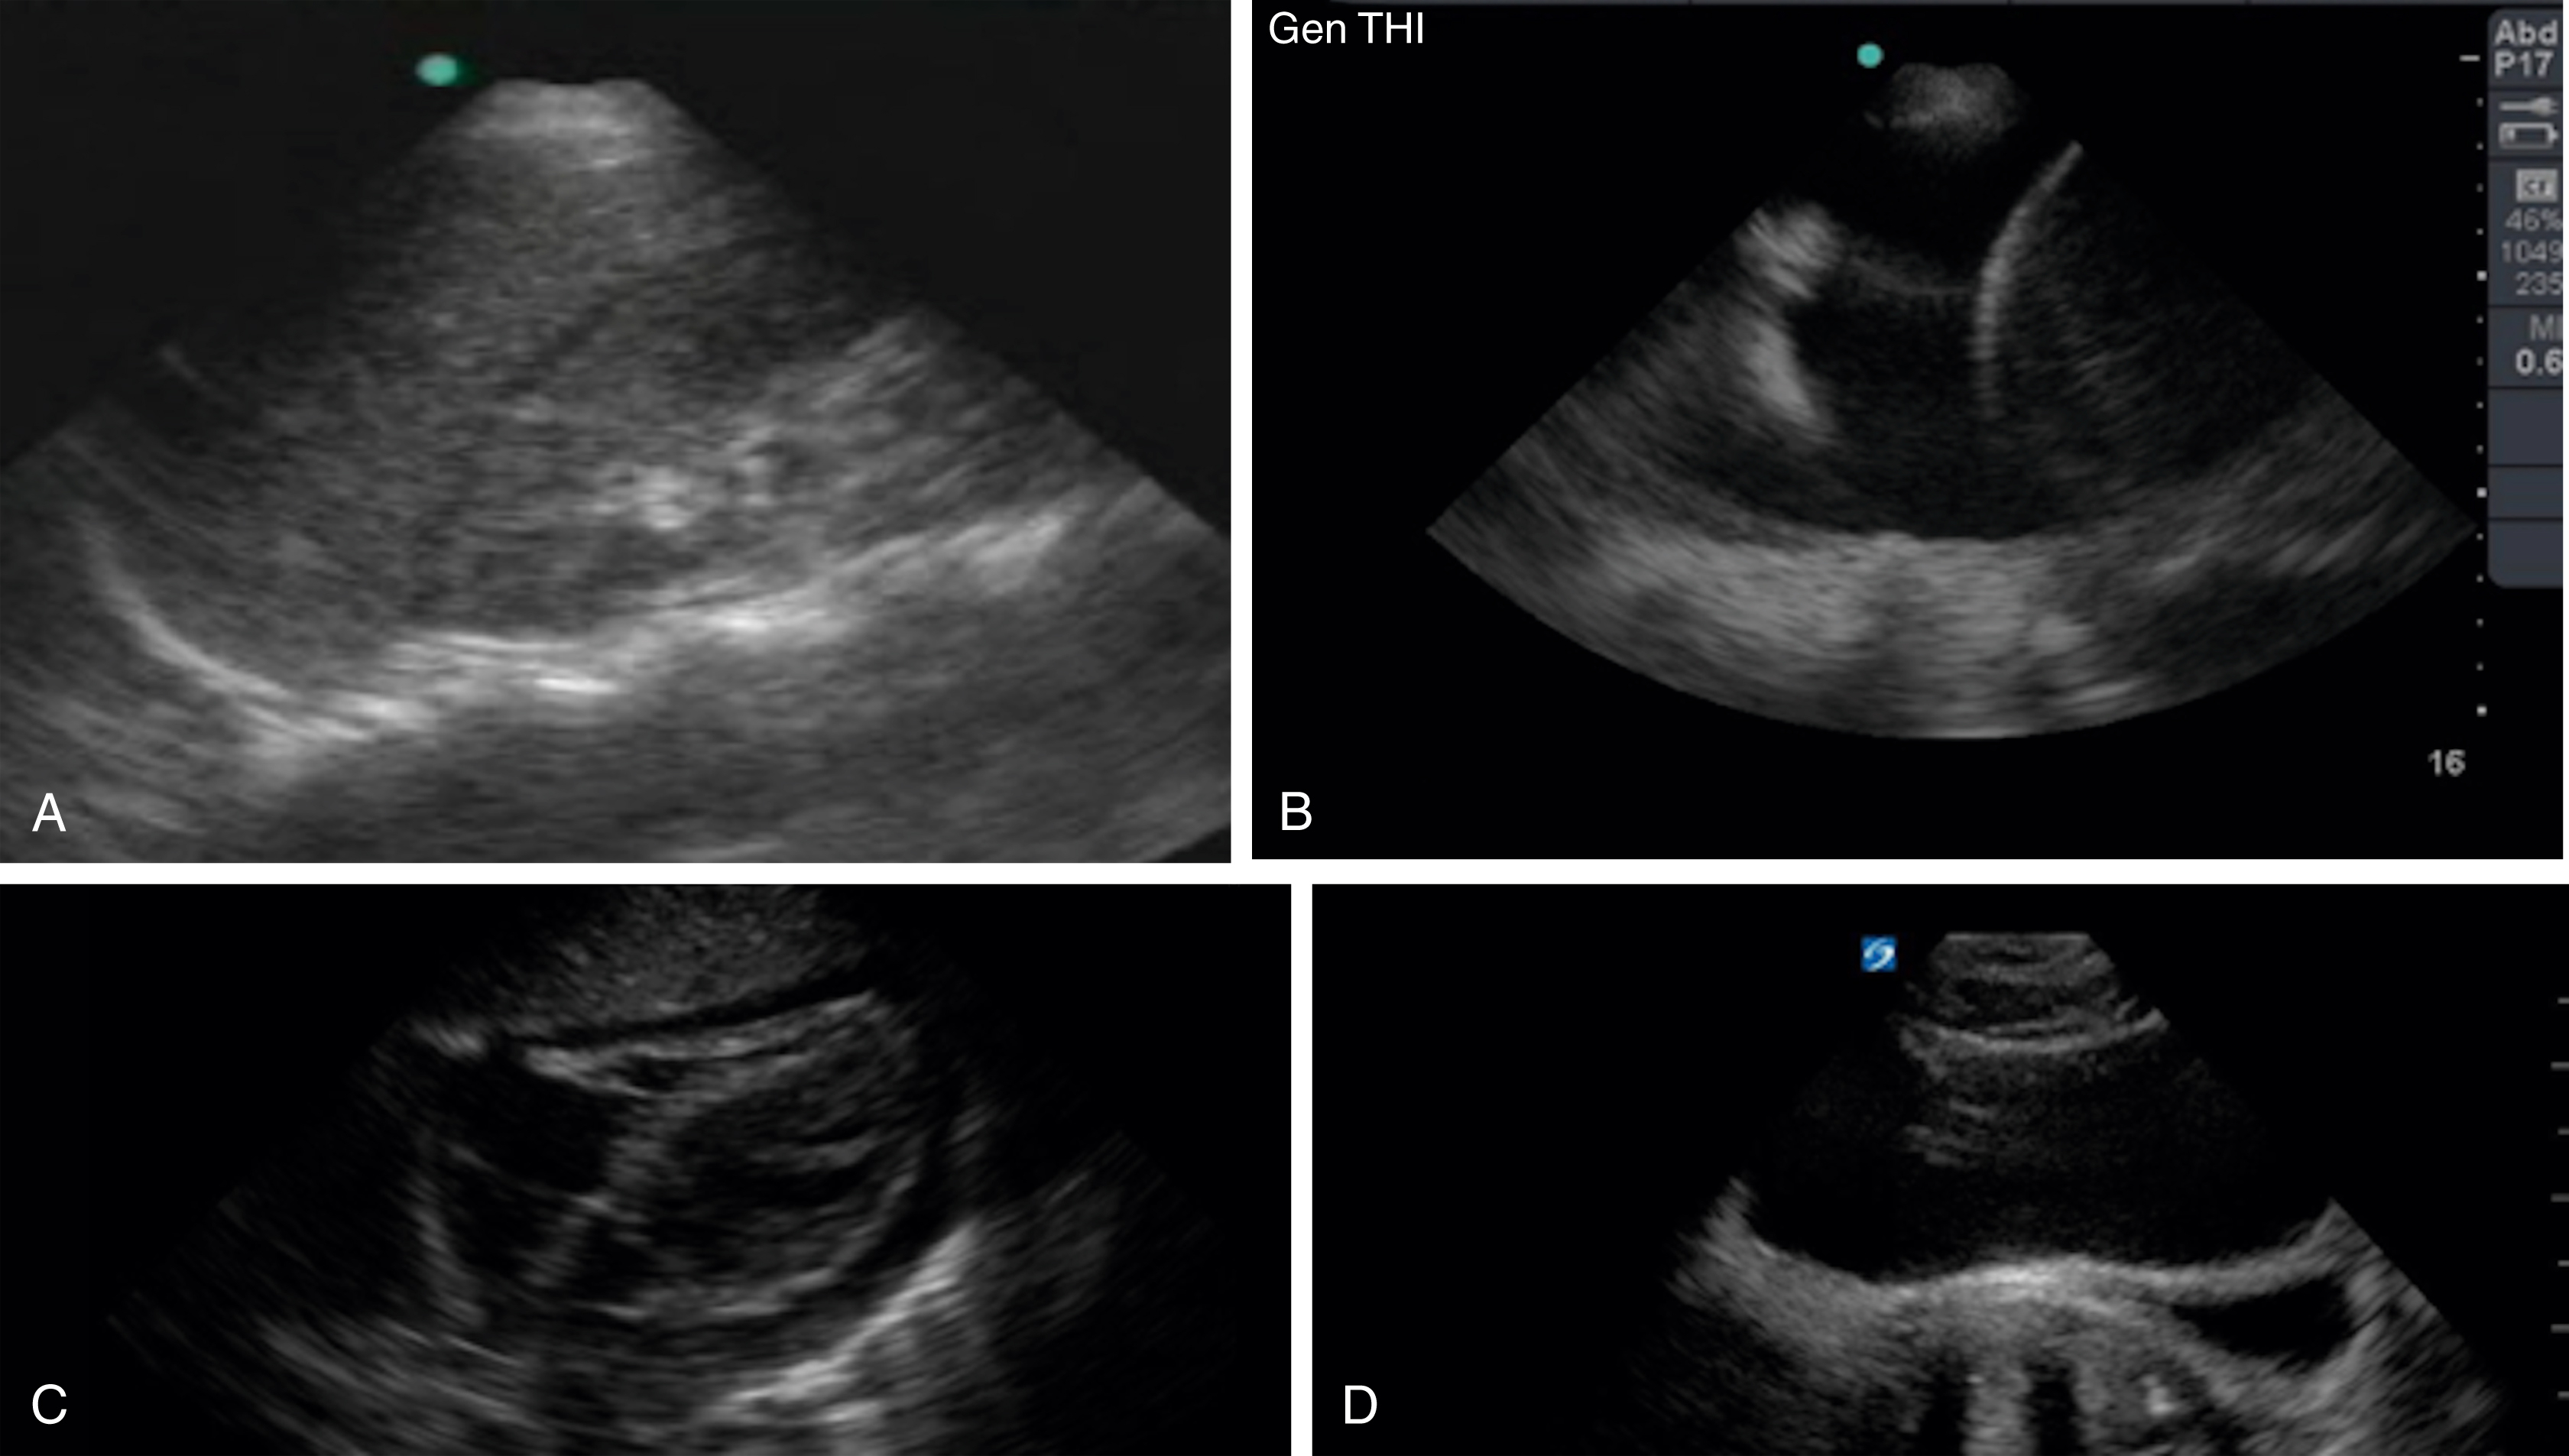

RV assessment is another useful tool for the emergency clinician when pulmonary embolism (PE) is high on the differential. With increasing right heart pressure, the RV dilates, squeezes poorly, and ultimately develops flattening of the interventricular septum, creating the “D” sign ( Figs. e3.12, e3.13 , and Video e3.11 ). The sparing of the RV apex is called the McConnell sign and is highly suggestive of PE. ,

Apical 4-chamber view of the heart with an enlarged RV.

Parasternal short axis view with “D” sign signifying increased RV pressure.

M mode images of the lung. (A) Normal lung with “seashore” sign. (B) Pneumothorax with “stratosphere” or “barcode” sign.